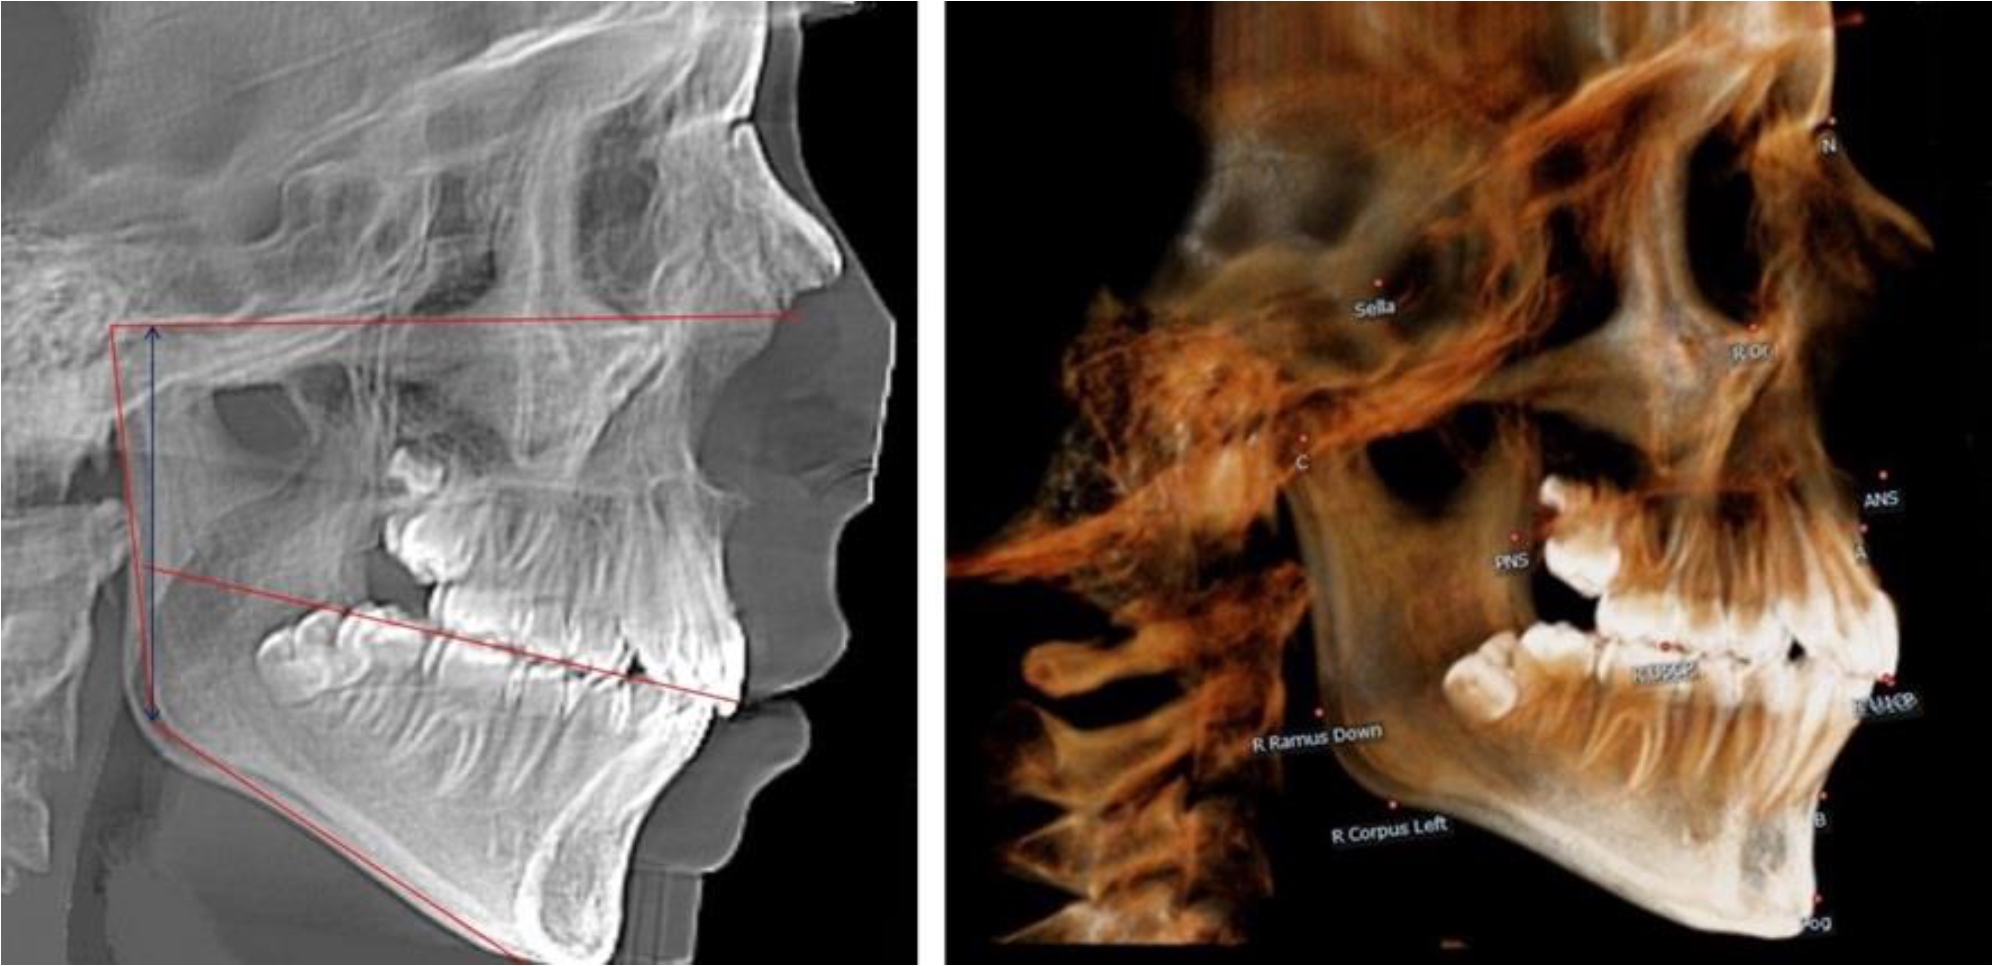

В 1-й группе были проанализированы 7 телерентгенограмм и 7 ортопантомограмм, что составило (6,60 ± 2,41) % от числа изученных рентгенограмм. На всех парах рентгенограмм угол нижней челюсти, измеренный на телерентгенограмме, соответствовал углу, полученному при построении угла на ортопантомограмме. Окклюзионная линия практически однотипно делила ветвь на два отдела (рис. 1).

Как на ортопантомограмме, так и на телерентгенограмме высота ветви у детей в периоде сформированного прикуса молочных зубов составляла (42,21 ± 2,48) мм. При этом высота верхней окклюзионно-суставной части была (22,57 ± 1,46) мм, а нижней – (19,64 ± 1,54) мм.

Учитывая вариабельность абсолютных величин, определи относительные показатели соразмерности частей ветви нижней челюсти. Так, отношение высоты верхней части ветви к нижней в среднем составляло 1,15 ± 0,13. Отношение общей высоты ветви к верхней ее части составляло 1,87 ± 0,14, а отношение общей высоты ветви к нижней ее части было 2,14 ± 0,16 и достоверных различий по относительному показателю отношения всей высоты к верхней и нижней челюсти нами не отмечено (р ˃ 0,05). При этом визуально обе части выглядели примерно равноразмерными.

Рис. 1. ТРГ и ОПТГ пациента 1-й группы